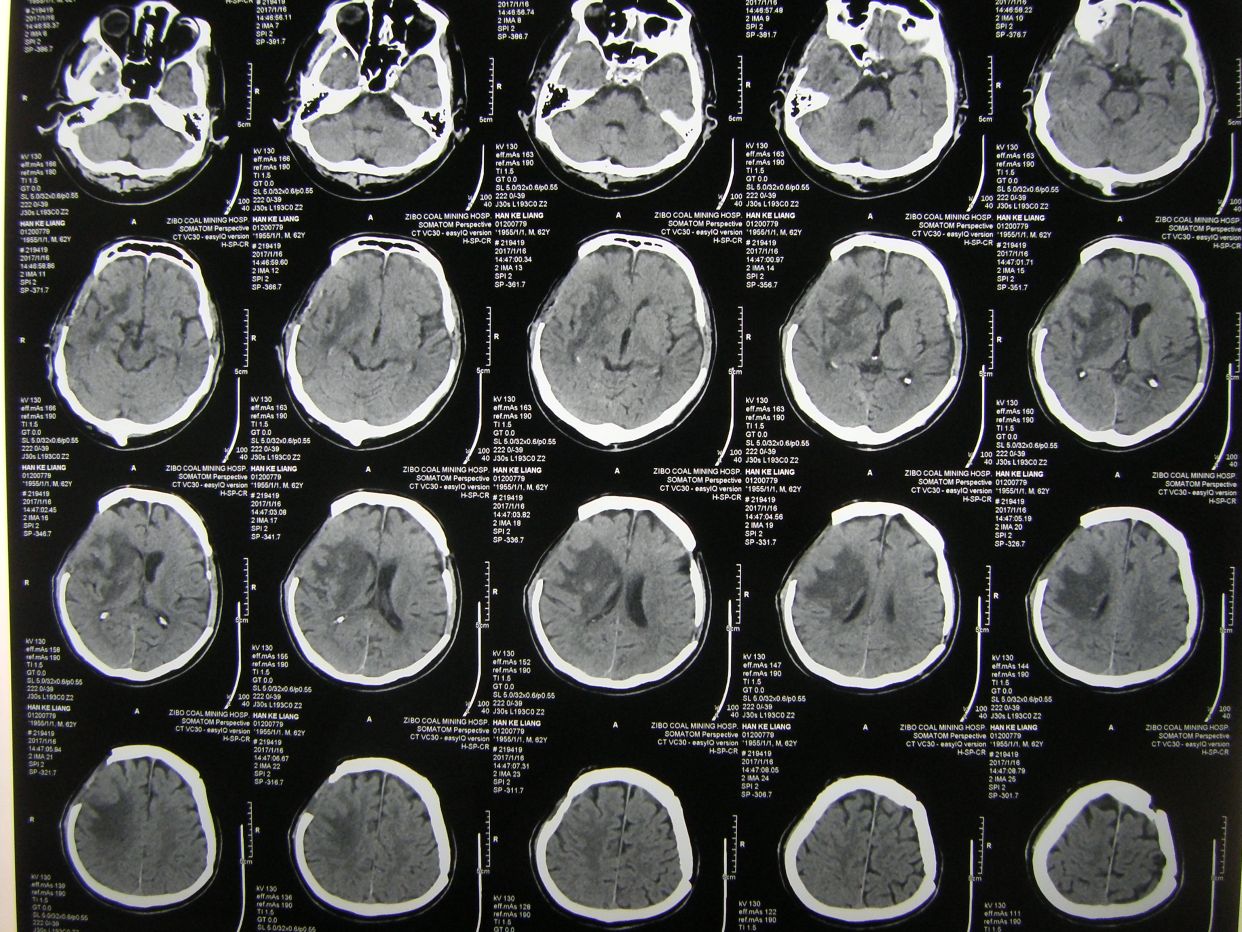

例1,男,61岁,言语不清伴左侧肢体活动障碍1小时入院。

CT示右基底节区脑出血,占位明显,中线移位。因出现右侧瞳孔增大,急症全麻下开颅血肿清除去骨瓣减压。

术后1天CT复查,血肿清除满意,中线恢复。

术后半月CT复查示,水肿基本消退,脑室无扩大。